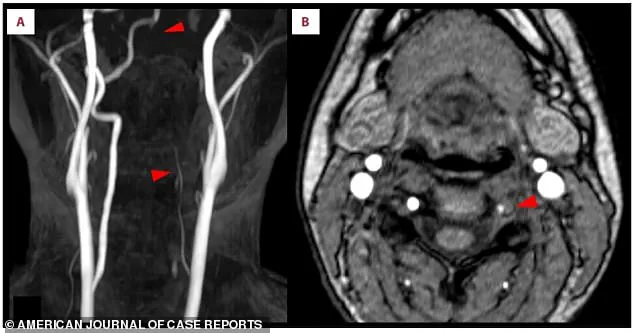

Medical imaging revealed the full extent of the damage.

In an MRI scan, bright white spots indicated acute ischemic stroke in the right occipital lobe, a sign of brain tissue deprived of oxygen.

Closer inspection of the scans showed a missing section of the right posterior cerebral artery, a critical vessel that supplies blood to the brain.

This absence pointed to a blockage, likely caused by a blood clot.

Further analysis of the left vertebral artery, a key artery in the neck that feeds the brain, showed it was faint and thin, suggesting restricted blood flow.

This discovery was a crucial clue in understanding the stroke’s origin.

The clot itself was confirmed in a second scan.

A crescent-shaped blood clot had formed inside the wall of the left vertebral artery, blocking blood flow and triggering the stroke.